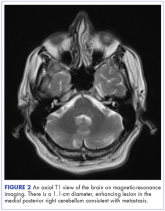

ArticleIntramedullary spinal cord and leptomeningeal metastases presenting as cauda equina syndrome in a patient with melanomaAuthor:Stephanie Lindhauer et alPublish date: September 7, 2017Read More